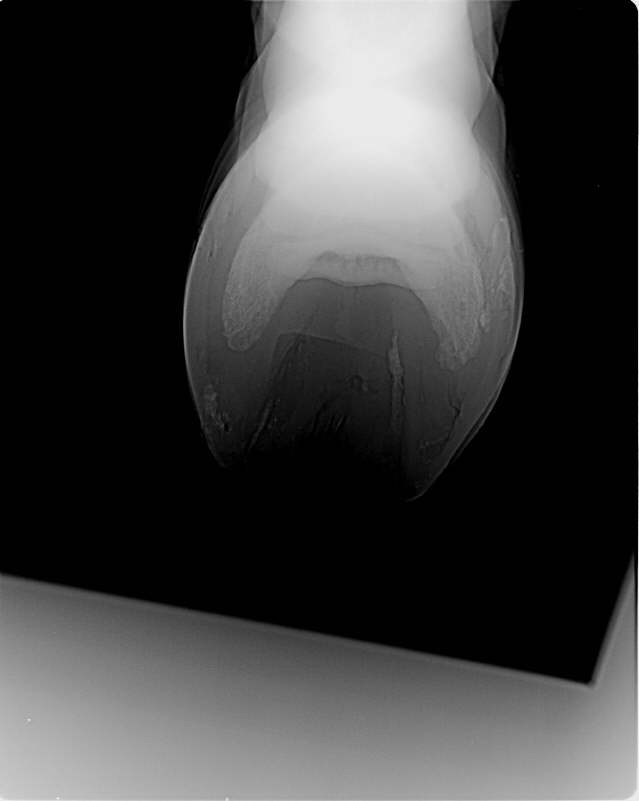

Deutliche Verstärkung der Gleitfläche und Abflachung der Gleitfläche